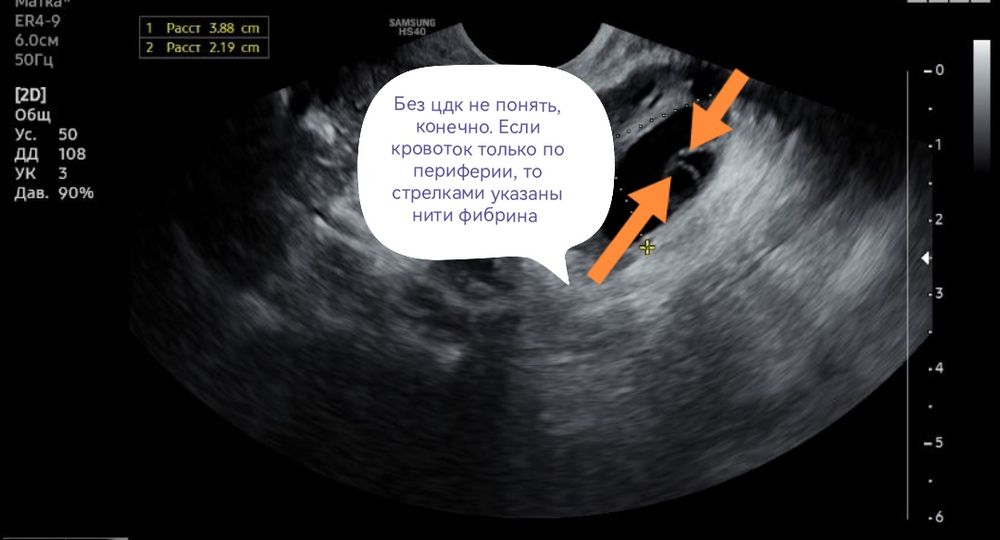

Узи и киста

Сказали киста желтого тела, но я не сильно доверяю, до этого она говорила что обычная киста от фоллика